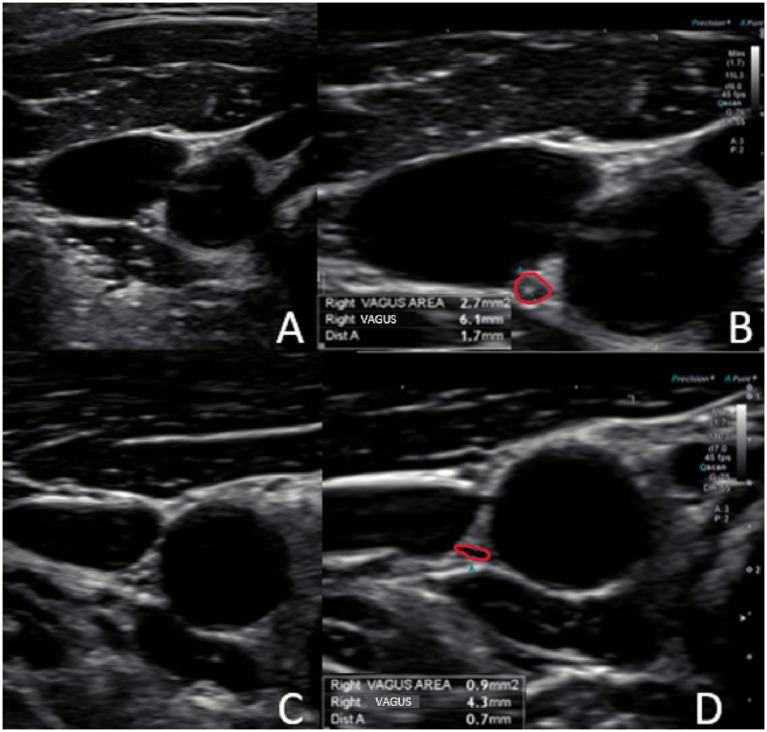

Vagus nerve dysfunction is implicated in the pathophysiology of many different symptoms and diseases that plague humanity. In many cases, the etiology of this condition remains elusive. One potentially implicating factor is cervical spine pathology, as the 2 vagus nerves are located in the carotid sheath just anterior to the cervical vertebrae. We propose that cervicovagopathy occurs primarily by the slow stretching of the posterior cervical ligaments because of a forward head-facedown lifestyle from excessive cell phone and computer usage. While the excessive stretch and compression on the vagus nerve initially just inhibits electrical impulses (conduction block), the condition progresses to ligamentous cervical instability. It ultimately results in a breakdown of the cervical curve (dysstructure), leading to vagus neuron cell death (degeneration), which can be documented by carotid sheath ultrasound. Cervical structural, internal jugular vein, and vagus nerve cross-sectional area measurements are presented from a retrospective chart review of 234 consecutive patients with no obvious cause for 1 of 9 specific symptoms-anxiety, dizziness, fatigue, irritability, lightheadedness, insomnia, sleeping difficulty, neck pain, and neck cracking/popping. Those cases of vagus nerve degeneration from a structural cause require corrective cervical structural therapies such as proper ergonomics, physiotherapy, cervical curve and postural exercises, low-force adjustments, and prolotherapy. A case example is given to demonstrate how cervical structural treatments can open up internal jugular veins and improve a patient's chronic symptoms. Resolution of symptoms that occur alongside improvements in vagus nerve cross-sectional areas (regeneration), correlating with restoration of the cervical lordotic curve and stability, will prove this hypothesis.

迷走神经功能障碍与困扰人类的许多不同症状和疾病的病理生理学有关。在许多情况下,这种病症的病因仍然难以捉摸。一个潜在的相关因素是颈椎病变,因为两条迷走神经位于颈椎前方的颈动脉鞘内。我们认为,由于过度使用手机和电脑导致的头前倾、脸朝下的生活方式,颈椎后韧带缓慢拉伸是导致颈迷走神经病变的主要原因。虽然迷走神经最初受到的过度拉伸和压迫只会抑制电冲动(传导阻滞),但病情会发展为颈椎韧带不稳定。最终会导致颈椎生理曲度破坏(结构紊乱),进而导致迷走神经神经元细胞死亡(变性),这可以通过颈动脉鞘超声检查记录下来。通过对234例连续患者的回顾性病历审查,给出了颈椎结构、颈内静脉和迷走神经横截面积的测量结果,这些患者没有明显原因出现以下9种特定症状中的一种:焦虑、头晕、疲劳、易怒、头晕目眩、失眠、睡眠困难、颈部疼痛以及颈部有弹响。那些由结构原因导致的迷走神经变性病例需要进行矫正颈椎结构的治疗,如适当的人体工程学调整、物理治疗、颈椎生理曲度和姿势锻炼、低力度调整以及注射治疗。给出了一个病例示例,以说明颈椎结构治疗如何能够扩张颈内静脉并改善患者的慢性症状。症状的缓解与迷走神经横截面积的改善(再生)同时出现,且与颈椎前凸曲线和稳定性的恢复相关,将证明这一假设。